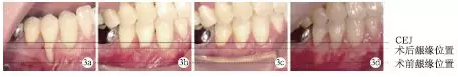

術(shù)前#44頰側(cè)牙齦退縮達(dá)9mm;術(shù)后兩周、術(shù)后兩個(gè)月及術(shù)后1年,頰側(cè)齦退縮減少為2mm,根面覆蓋率為:77.8%,未見(jiàn)進(jìn)行性牙齦退縮(圖3)。

圖3 術(shù)前及術(shù)后根面牙齦覆蓋情況對(duì)比

術(shù)前#44頰側(cè)角化齦寬度極少,小于1mm;術(shù)后2個(gè)月及術(shù)后1年,可見(jiàn)角化齦寬度增加為2mm,且角化齦厚度也明顯增加,見(jiàn)圖4。

圖4 術(shù)前及術(shù)后頰側(cè)角化齦寬度對(duì)比